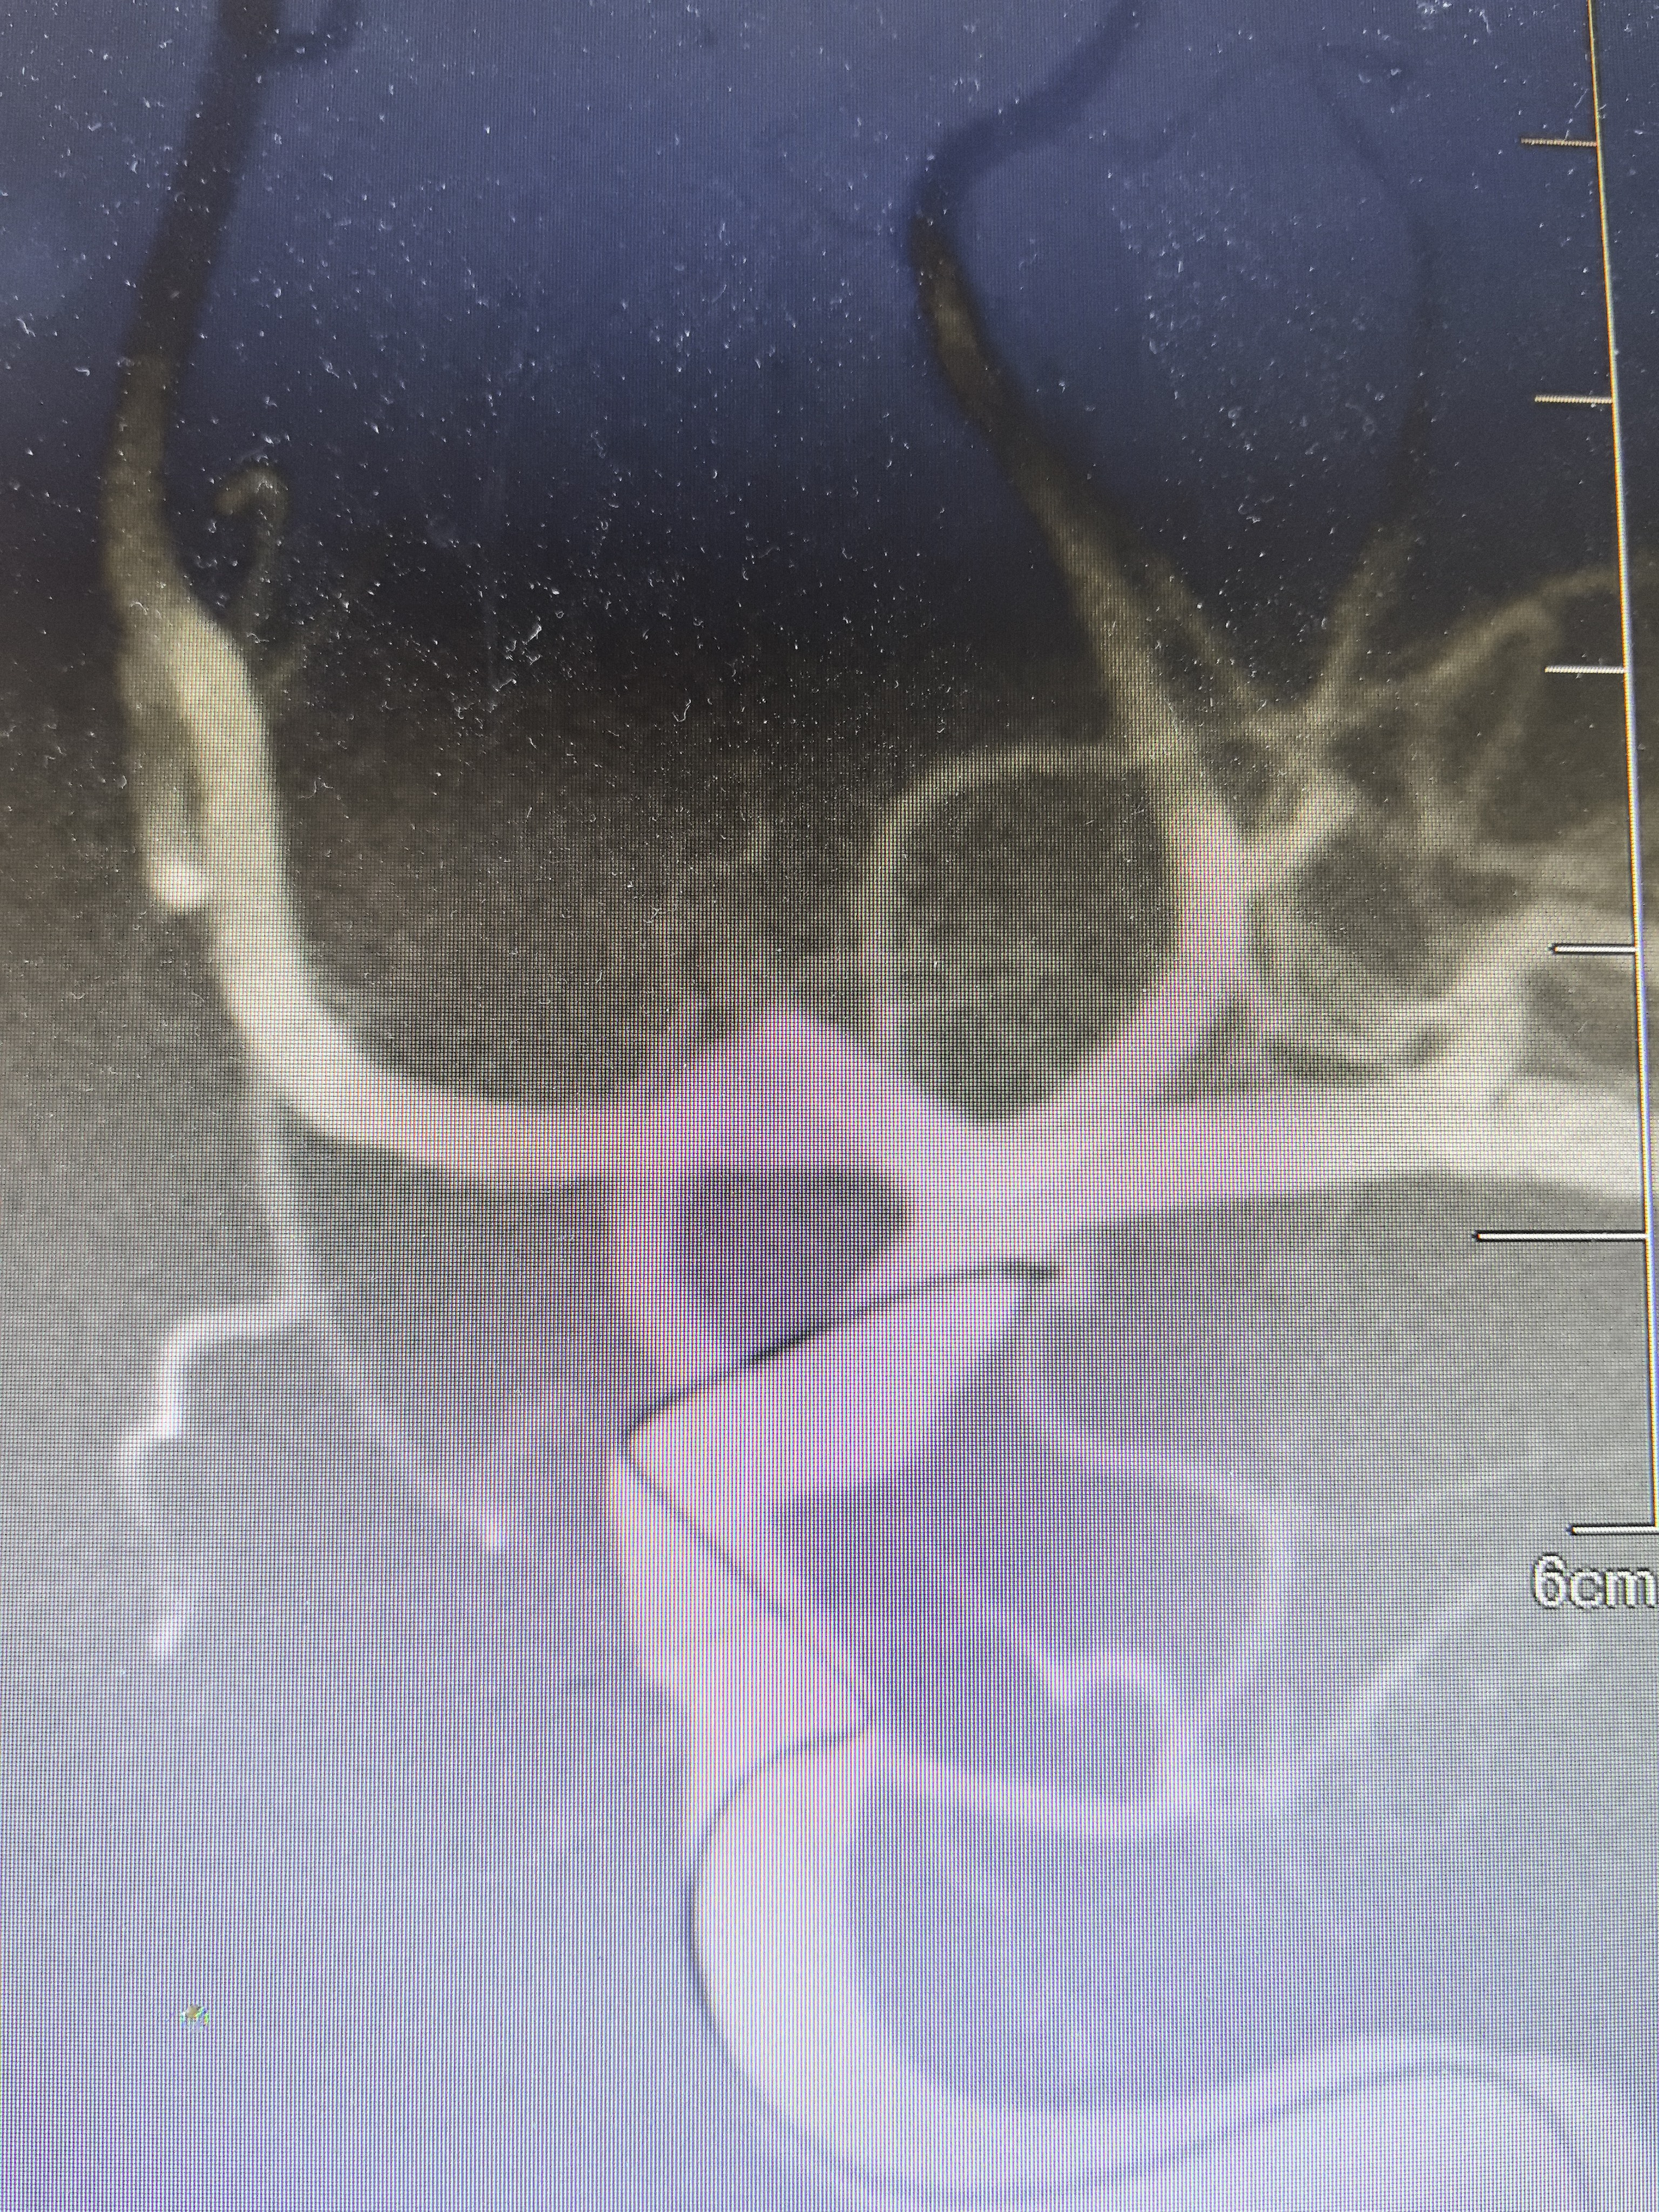

弹簧圈尝试栓塞

解脱弹簧圈后微导管弹出

造影显示动脉瘤栓塞满意,术闭。